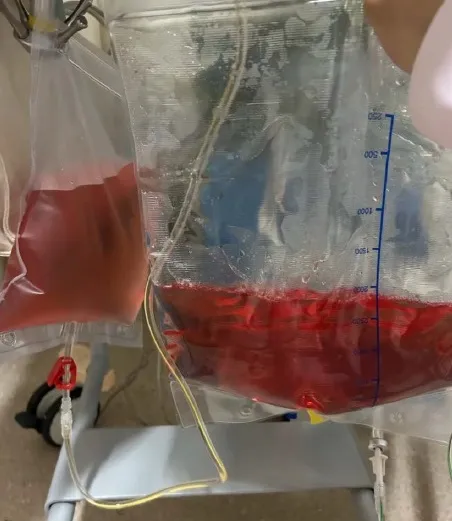

IRA + Icterícia: Um Caso que Exige Investigação Detalhada

IRA + Icterícia: Um Caso que Exige Investigação Detalhada